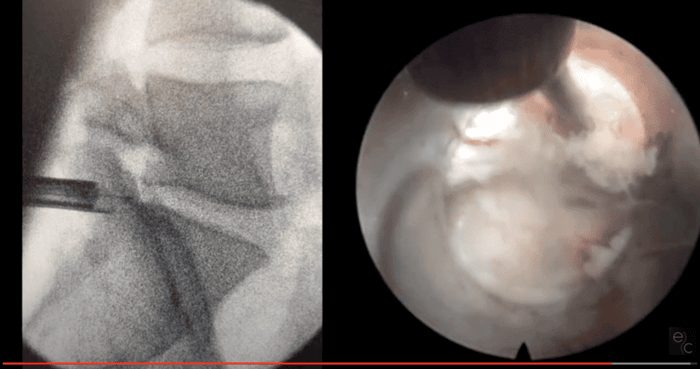

Tipos de cirugía: microdiscectomía y cirugía endoscópica

Existen diferentes enfoques quirúrgicos para tratar la hernia discal, desde procedimientos mínimamente invasivos hasta técnicas más tradicionales como la microdiscectomía, que buscan aliviar la presión sobre los nervios comprimidos.

Una de las ventajas más destacadas de la cirugía endoscópica en comparación con la microdiscectomía en el tratamiento quirúrgico de la hernia discal es su carácter ultra mínimamente invasivo.

La cirugía endoscópica utiliza incisiones mucho más pequeñas (alrededor de 7 milímetros), lo que reduce significativamente el daño a los tejidos circundantes y, como resultado, disminuye el dolor postoperatorio y acelera la recuperación del paciente.

Además, esta técnica permite una mejor visualización del área afectada a través de un endoscopio, lo que puede aumentar la precisión del cirujano y reducir el riesgo de complicaciones. Esto se traduce en menos días de hospitalización y una reincorporación más rápida a las actividades diarias y laborales, mejorando así la calidad de vida del paciente.